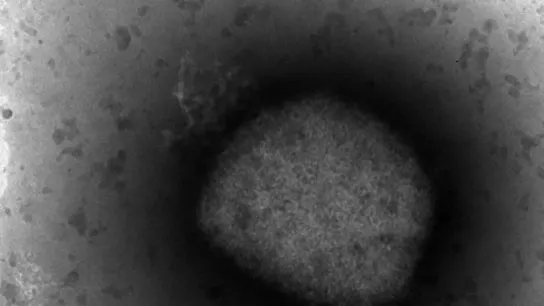

Así se ve en el microscopio

La secuenciación completa confirma que el virus de la viruela del mono del brote que se está produciendo en España pertenece a un grupo fitogenético de África Occidental. Un logro de los investigadores del Instituto de Salud Carlos III.

La secuenciación completa ha confirmado que el virus de la viruela de los monos del brote que se está produciendo en España pertenece a un grupo fitogenético de África Occidental, que es el de menor virulencia entre los conocidos y el que se ha identificado por el momento en la mayoría de los países fuera de África implicados en este brote.

La secuenciación confirma que el virus de la viruela de los monos del brote que se está produciendo en España pertenece al "clado" -variante- de África Occidental.

Los "clados", ha informado el Instituto, son grupos filogenéticos que definen la evolución biológica de un organismo, que explican cómo actúa y se comporta, y en ellos se pueden observan las diferencias genéticas de los virus circulantes.